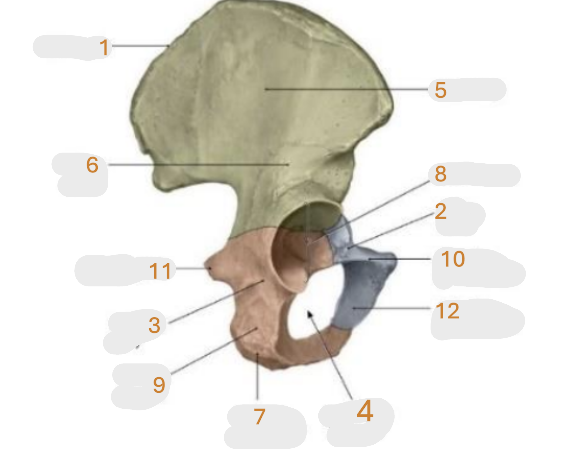

Where is the posterior inferior iliac spine

1

Where is the gluteal surface

2

Where is the iliac crest

3

Where is the posterior superior iliac spine

4

Where is the anterior gluteal line

5

Where is the anterior superior iliac spine

6

Where is the greater sciatic notch

7

Where is the inferior gluteal line

8

Where is the ischial spine

9

Where is the acetabular rim

10

Where is the lesser sciatic notch

11

Where is the obturator foramen

12

Where is the ischial tuberosity

13

Where is the anterior inferior iliac spine

14

Where is the acetabular notch

15

Where is the acetabulum

16

Where is the lunate surface

17

Where is the pubic tubercle

18

Where is the acetabular fossa

19